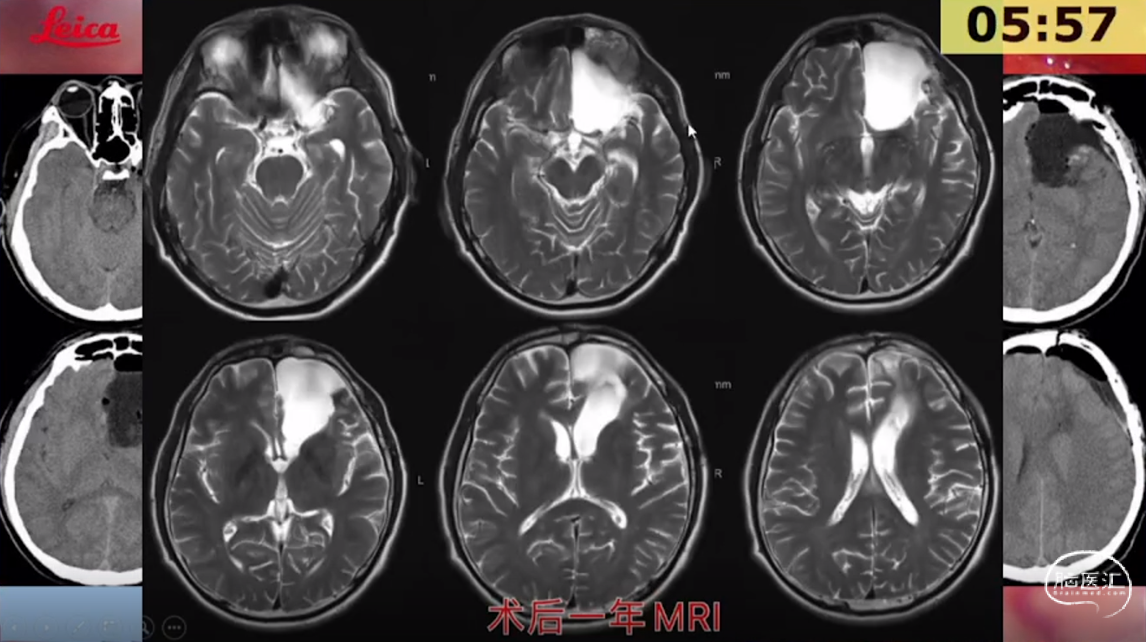

刘宏毅教授:脑网络的构建及在脑胶质瘤诊疗中应用初探

讲题:脑网络的构建及在脑胶质瘤诊疗中应用初探